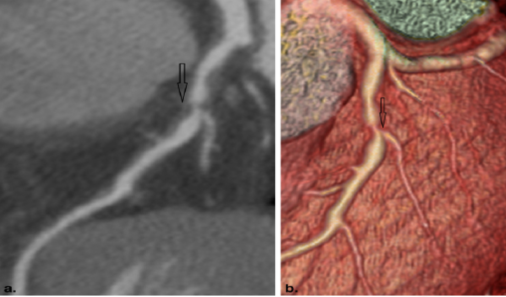

冠状动脉CT血管成像示冠状动脉斑块形成,导致冠状动脉管腔狭窄,明确诊断冠心病

医生靠什么评估冠心病:1.心电图:大部分冠心病病人,没有症状发作时的心电图都是基本正常。所以,心电图正常不能排除冠心病。当出现心绞痛症状时,发生暂时的T波倒置,或ST段下移。心电图运动试验更加准确,通过运动增加心脏负担,在负荷的情况下观察会不会出现上述心肌缺血的心电图表现。2.影像学检查:包括心脏超声,冠状动脉CT血管成像,心脏核磁共振(MRI),核医学心肌灌注检查等。各种影像学检查各有优势,医生会根据您的病情选择合适的检查方法,目前应用比较广泛的是心脏超声和冠状动脉CT血管成像检查,特别是冠状动脉CT血管成像检查,可以直接观察到冠状动脉内是否存在斑块及血管狭窄,提供诊断冠心病的直接证据。当然,目前诊断冠心病的金标准还是经导管的冠状动脉造影检查,该检查属于有创检查,必须住院在医院导管室内完成,存在一定的风险性。可喜的是,上述冠状动脉CT血管成像等无创的影像学检查可以在门诊完成,且可以明确是否存在冠心病。故当您怀疑到自己存在冠心病时,一定不要讳疾忌医,及时就诊,让医生判断病情,早诊早治,以免延误病情。